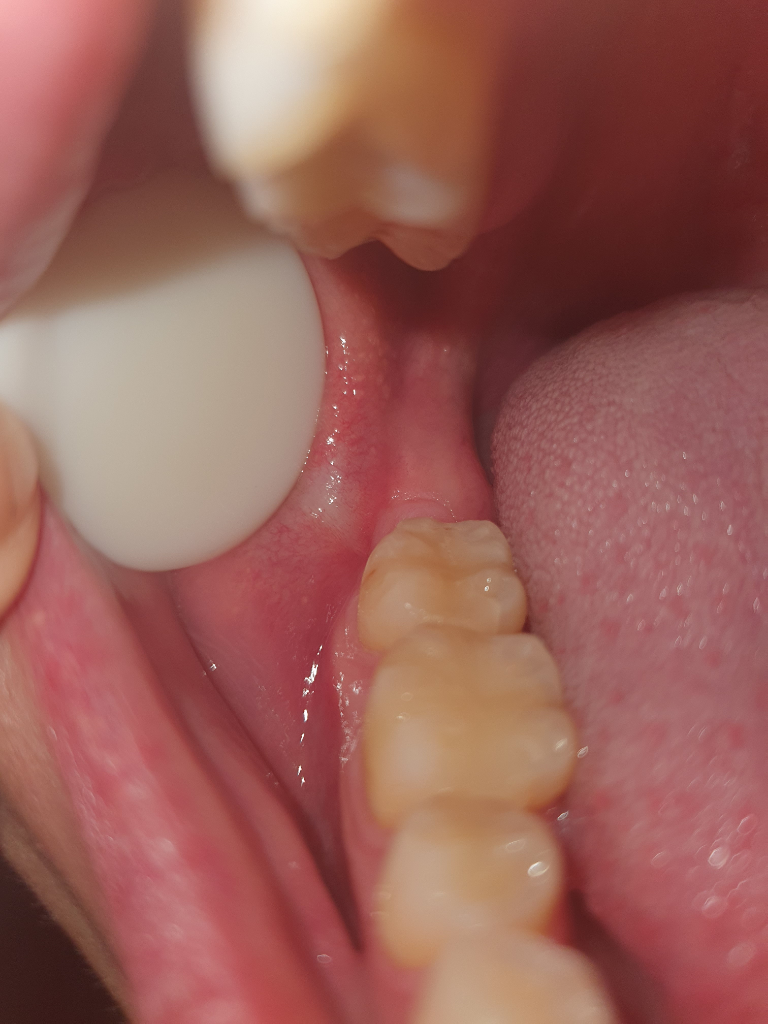

사랑니 발치한곳에 음식물이없는데 끼인느낌이 들어요

사랑니 발치한지 5개월 정도 됬습니다.

매복 수평 사랑니여서 뽑을때 엄청 힘들게 뽑았습니다.

그래서 그런지 발치후 한달쯤 되던날 아래쪽 빌치한곳 잇몸에 누런 고름이 차서 근처병원에서 소독밑 약을 받아 관리후 문제 없다는 의사선생님의 말씀을 들었습니다.

근데 어느날 부터 음식물을 먹고난 이후로 사랑니 발치한 아래쪽 잇몸에 뭔가 끼인느낌과 불편한 느낌이 들고 귀밑 턱 쪽에도 심하진 않지만 뻐근하고 신경쓰이는 느낌이 계속들다가

어느날 잇몸을 보니 잇몸이 조금 부어오른것처럼 구분이 되어져 보이는데 혹시 고름이 차서 치주농양이 된걸까요?

앞쪽어금니에는 특별한 통증이나 불편함은 없고 평소 치실도 자주 사용하여 잇몸에 피가나거나 하지는 않습니다.

그냥 계속 끼인느낌과 신경쓰이는 느낌만 드는데 이거 심각한건지 궁금하여 질문 남깁니다.

• 1번 째 사진

치과 방문이 필요합니다. 어금니 뒤쪽에 농양이 있을 가능성이 매우 높습니다. 사랑니 발치로 인하여 나타난 농양이라고 무조건 할 수는 없으며 앞쪽 어금니에 의해서 나타날 수도 있어 보입니다. 잇몸이 부어 있고 해당 부위에 농이 있을 가능성이 크므로 이를 제거하는 것이 맞아 보입니다. 치과를 빨리 방문하시길 바랍니다.

사진상으로는 크게 문제가 없어 보입니다. 사랑니 발치한곳보다는 그 앞쪽치아 뒷편에 염증이 생겻을 가능성이 잇으니 치과에 가셔서 그쪽잇몸치료를 한번 받아보세요.

사진으로 봤을 경우에는 큰 문제가 보이지는 않습니다.

사랑니를 발치하고 내부에 생긴 공간으로 이물질이 들어가서 나오지 못하는경우에 내부에서 염증을 이일으키는 경우가 있기 때문에 이런경우에는 염증을 줄어주기 위햇 원인을 제거해야 해요.

방사선 사진을 찍어서 확인을 해봐야 할것으로 생각됩니다.